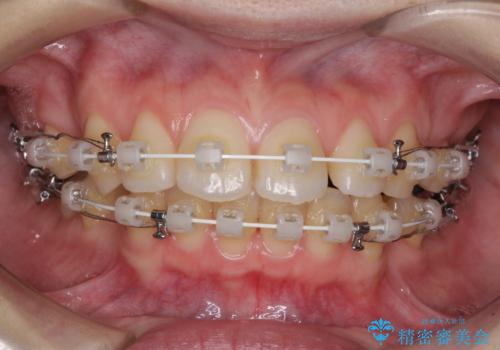

- 審美装置

上下左右第一小臼歯4本を抜歯し、ワイヤー装置にて口元を引っ込めるよう矯正治療を行うこととしました。